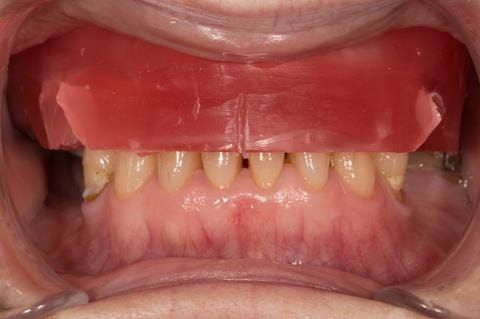

- Cobalt chromium reinforced gasket denture - using a Molloplast B "O" ring to retain and stabilise the denture. This was my professional preference as this was the least invasive and simplest solution to this dental problem. Should the UR7 require removal in the future - an artificial tooth could be added - resulting in a complete denture. The patient would have adapted to the denture fully by this stage and have good neuromuscular control of the prosthesis.

Following consultation and second discussion appointment the patient chose to have option 2 namely, a window denture - maxillary cobalt chromium based partial denture. The clinical situation and treatment process is shown in detail below with photographs. The patient was successfully rehabilitated with this and her quality of life considerably improved. The clinical work was provided by Finlay and the technical work by Rowan.